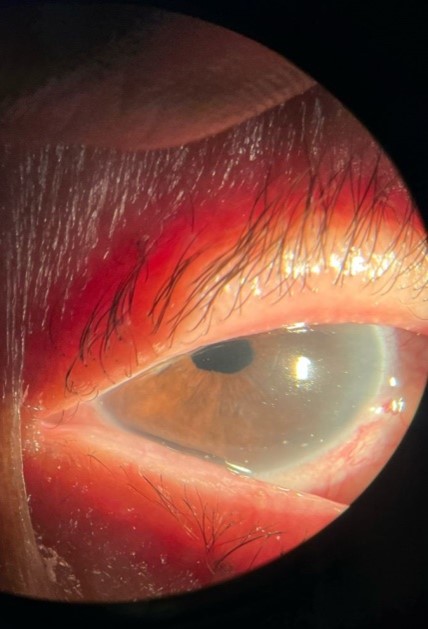

On postoperative day one, the patient presented with counting fingers visual acuity, epiphora, and marked corneal edema involving nearly two-thirds of the lateral cornea (Figure 1). Intraocular pressure was 16 mmHg.

Figure 1: Slit-lamp image of the right eye on postoperative day one showing extensive corneal edema corresponding to the zone of Descemet’s membrane detachment (DMD). The red arrow indicates the margin between the clear cornea and the ruptured zone of Descemet.